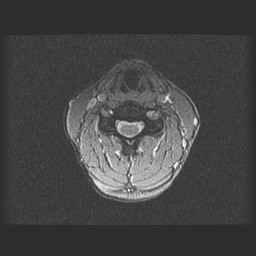

CWZ